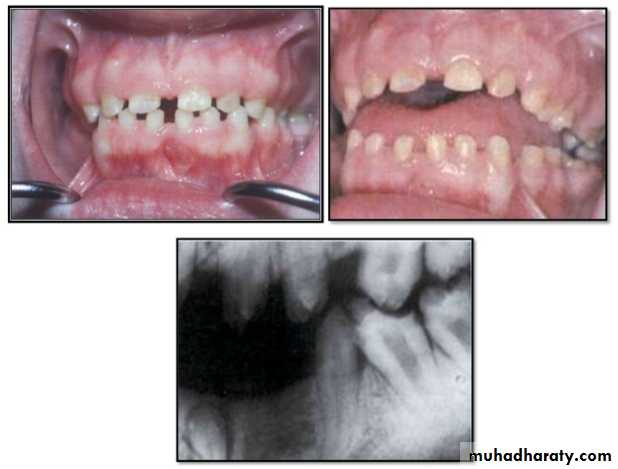

Hypoplastic Amelogenesis Imperfecta:

* Due to some defect in ameloblasts enamel fails to develop to its normal thickness dentin exposed the tooth shows yellowish-brown color.*Enamel is randomly:

pitted .

rough OR smooth &glossy.

*The occlusal surfaces of the posterior teeth are relatively

flat with low cusps due to attrition of cusp tips that were initially low and not fully formed. An anterior open bite may be noted..

Generalized hypoplastic type

Amelogenesis ImperfectaAffects primary &permenant dentition

Severe mottling of the enamel surface.